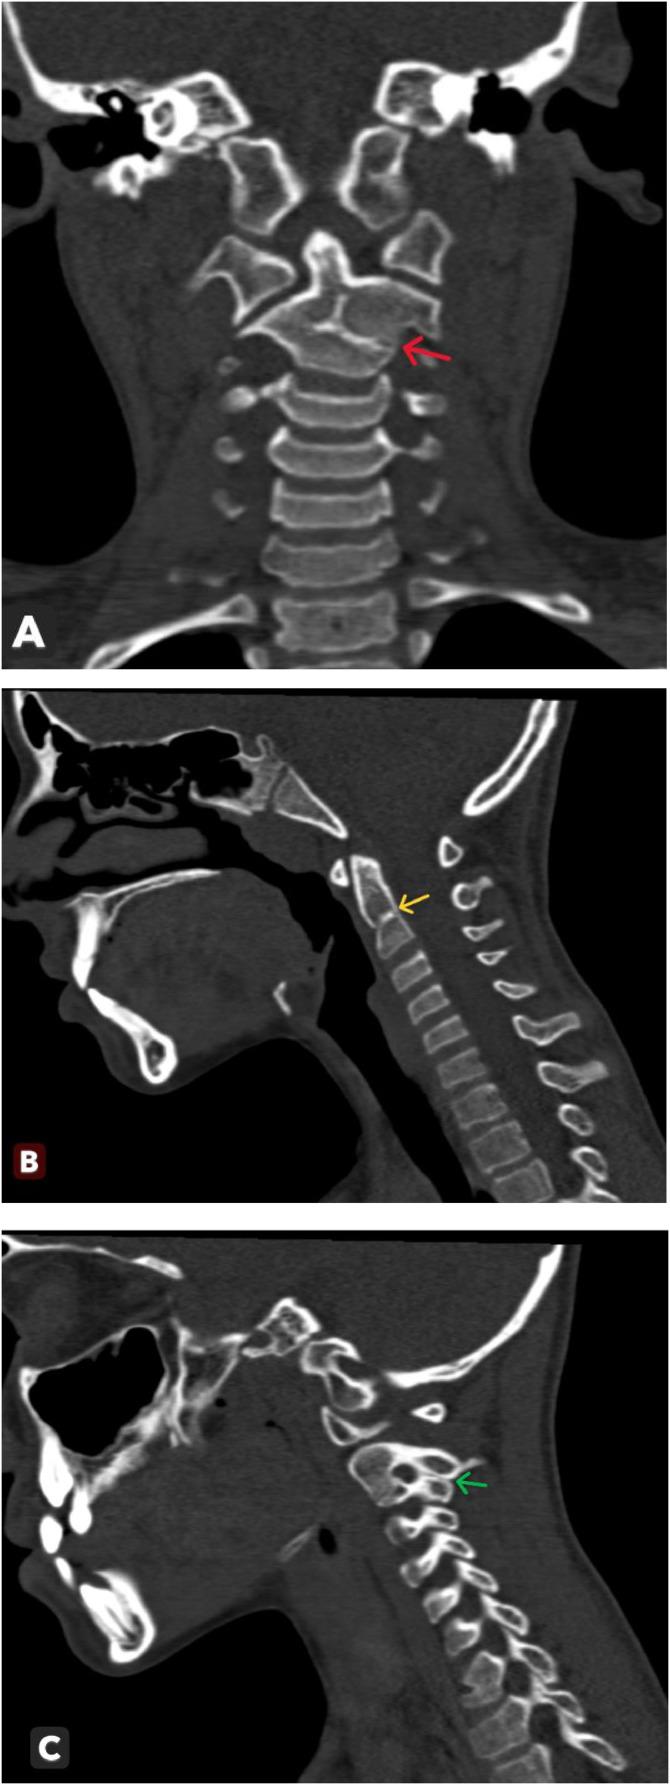

Klippel-Feil syndrome (KFS) is a congenital anomaly involving the fusion of two or more cervical vertebrae. It is characterized by a low hairline at the nape of the neck, a short neck, and a limited range of motion. Here, we present the case of a 10-year-old girl who suffered brain trauma in a motor vehicle accident and subsequently experienced persistent occipital headaches and dizziness. A brain computed tomography scan performed to evaluate these symptoms revealed incomplete fusion of two cervical vertebrae (C2-C3), leading to a diagnosis of KFS. Magnetic resonance imaging of the spine was conducted to investigate potential spinal abnormalities. In this article, we discuss the pathogenesis, associated abnormalities, subtypes, complications, and differential diagnosis of KFS. There is no cure for KFS. Treatment requires a multidisciplinary approach involving neurologists, orthopedic surgeons, pediatricians, physical therapists, and neurosurgeons, depending on the severity of the symptoms.

克-费综合征(KFS)是一种涉及两个或更多颈椎融合的先天性异常。其特征为颈后部发际线低、颈部短以及活动范围受限。在此,我们报告一例10岁女孩的病例,该女孩在机动车事故中遭受脑外伤,随后持续出现枕部头痛和头晕。为评估这些症状而进行的脑部计算机断层扫描显示两个颈椎(C2-C3)融合不全,从而诊断为KFS。进行了脊柱磁共振成像以调查潜在的脊柱异常。在本文中,我们讨论了KFS的发病机制、相关异常、亚型、并发症及鉴别诊断。KFS无法治愈。治疗需要多学科方法,根据症状的严重程度,涉及神经科医生、骨科医生、儿科医生、物理治疗师和神经外科医生。